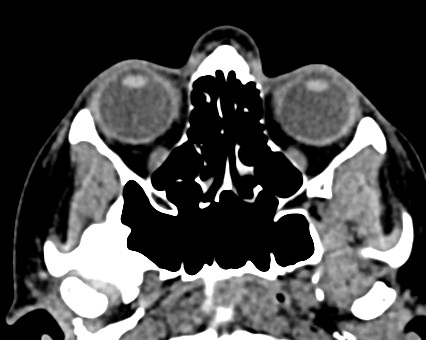

Орбиты (или глазницы) – это костные углубления в лицевом черепе, где расположены глазные яблоки, окруженные жировой клетчаткой, а также слезные железы, слезные каналы, сосуды, нервы, мышцы и связки глаза. Такая небольшая по объему область содержит важные анатомические структуры, обеспечивающие нормальную функцию органа зрения.

Кроме того, область орбиты тесно связана с близлежащими структурами – полостью черепа с расположенным в ней головным мозгом, а также с полостью носа, околоносовыми пазухами и носоглоткой. Различные патологические процессы могут развиваться как в самой глазнице, так и в околоорбитальных структурах, но при этом распространяться на область орбит.

Сложное строение глазницы и взаимосвязь с соседними анатомическими структурами затрудняет диагностику заболеваний глазного яблока и его придатков. Одним из наиболее информативных методов обследования органа зрения и окружающих тканей является мультиспиральная компьютерная томография. Кроме высокой информативности методика отличается быстротой и неинвазивностью (то есть не требует вмешательства в организм человека). Принцип получения изображений построен на применении ионизирующего излучения и разной способности тканей поглощать рентгеновские лучи.

Мультиспиральная компьютерная томография лучше всего визуализирует ткани с высокой плотностью, к которым, в частности, относится костная ткань. Это делает КТ незаменимой при диагностике травматических повреждений глазниц, а также для выявления инородных тел орбит.

Для более детальной визуализации мягкотканных структур дополнительно применяется контрастное усиление. Для этого пациенту внутривенно вводится йодсодержащий контрастный препарат, благодаря которому становятся видны патологические образования размером до 1 мм. Методика позволяет обнаружить патологию еще до появления симптомов заболевания, когда лечение наиболее эффективно.

По результатам КТ орбиты глаза врач может оценить состояние:

- костных стенок глазницы, верхней и нижней глазничных щелей;

- глазных яблок

- стекловидного тела;

- мышц глаза: нижней, верхней, косой, прямых мышц (латеральной и медиальной);

- глазничной артерии и вены;

- зрительных нервов;

- слезных желез;

- ретробульбарной (расположенной позади глазного яблока) клетчатки.

КТ орбит позволяет выявить:

- инородные тела в глазницах;

- воспалительные заболевания;

- поражения зрительного нерва;

- доброкачественные и злокачественные образования (опухоли); метастазы

- переломы стенок глазниц;

- поражения орбитальных сосудов и мышц.

- гематомы;

- псевдотумор (псевдоопухоль) – воспаление мягких тканей орбиты предположительно аутоиммунного происхождения;

- склероз тканей орбиты (результат воспалительного процесса).